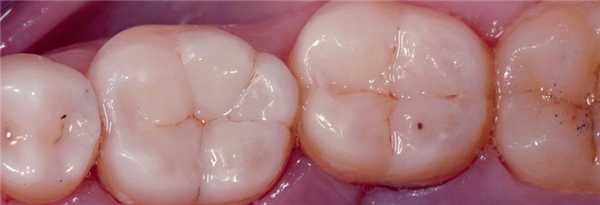

Фото 7. Вид после контурирования и полировки реставраций.

Фото 12. Вид после контурирования и полировки реставраций.